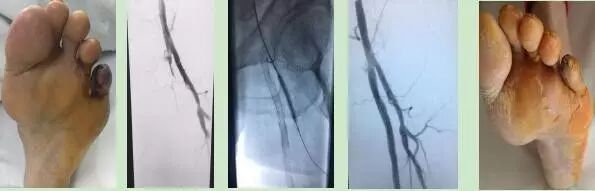

2、下肢动脉疾病:各种下肢缺血疾病所致的下肢疼痛跛行或溃烂,如下肢动脉硬化狭窄或闭塞症,脉管炎、急慢性动脉血栓形成和栓塞、糖尿病足等。

下肢动脉硬化闭塞症的腔内及杂交手术治疗杂交手术治疗动脉硬化闭塞症

腔内支架植入术开通下肢血管